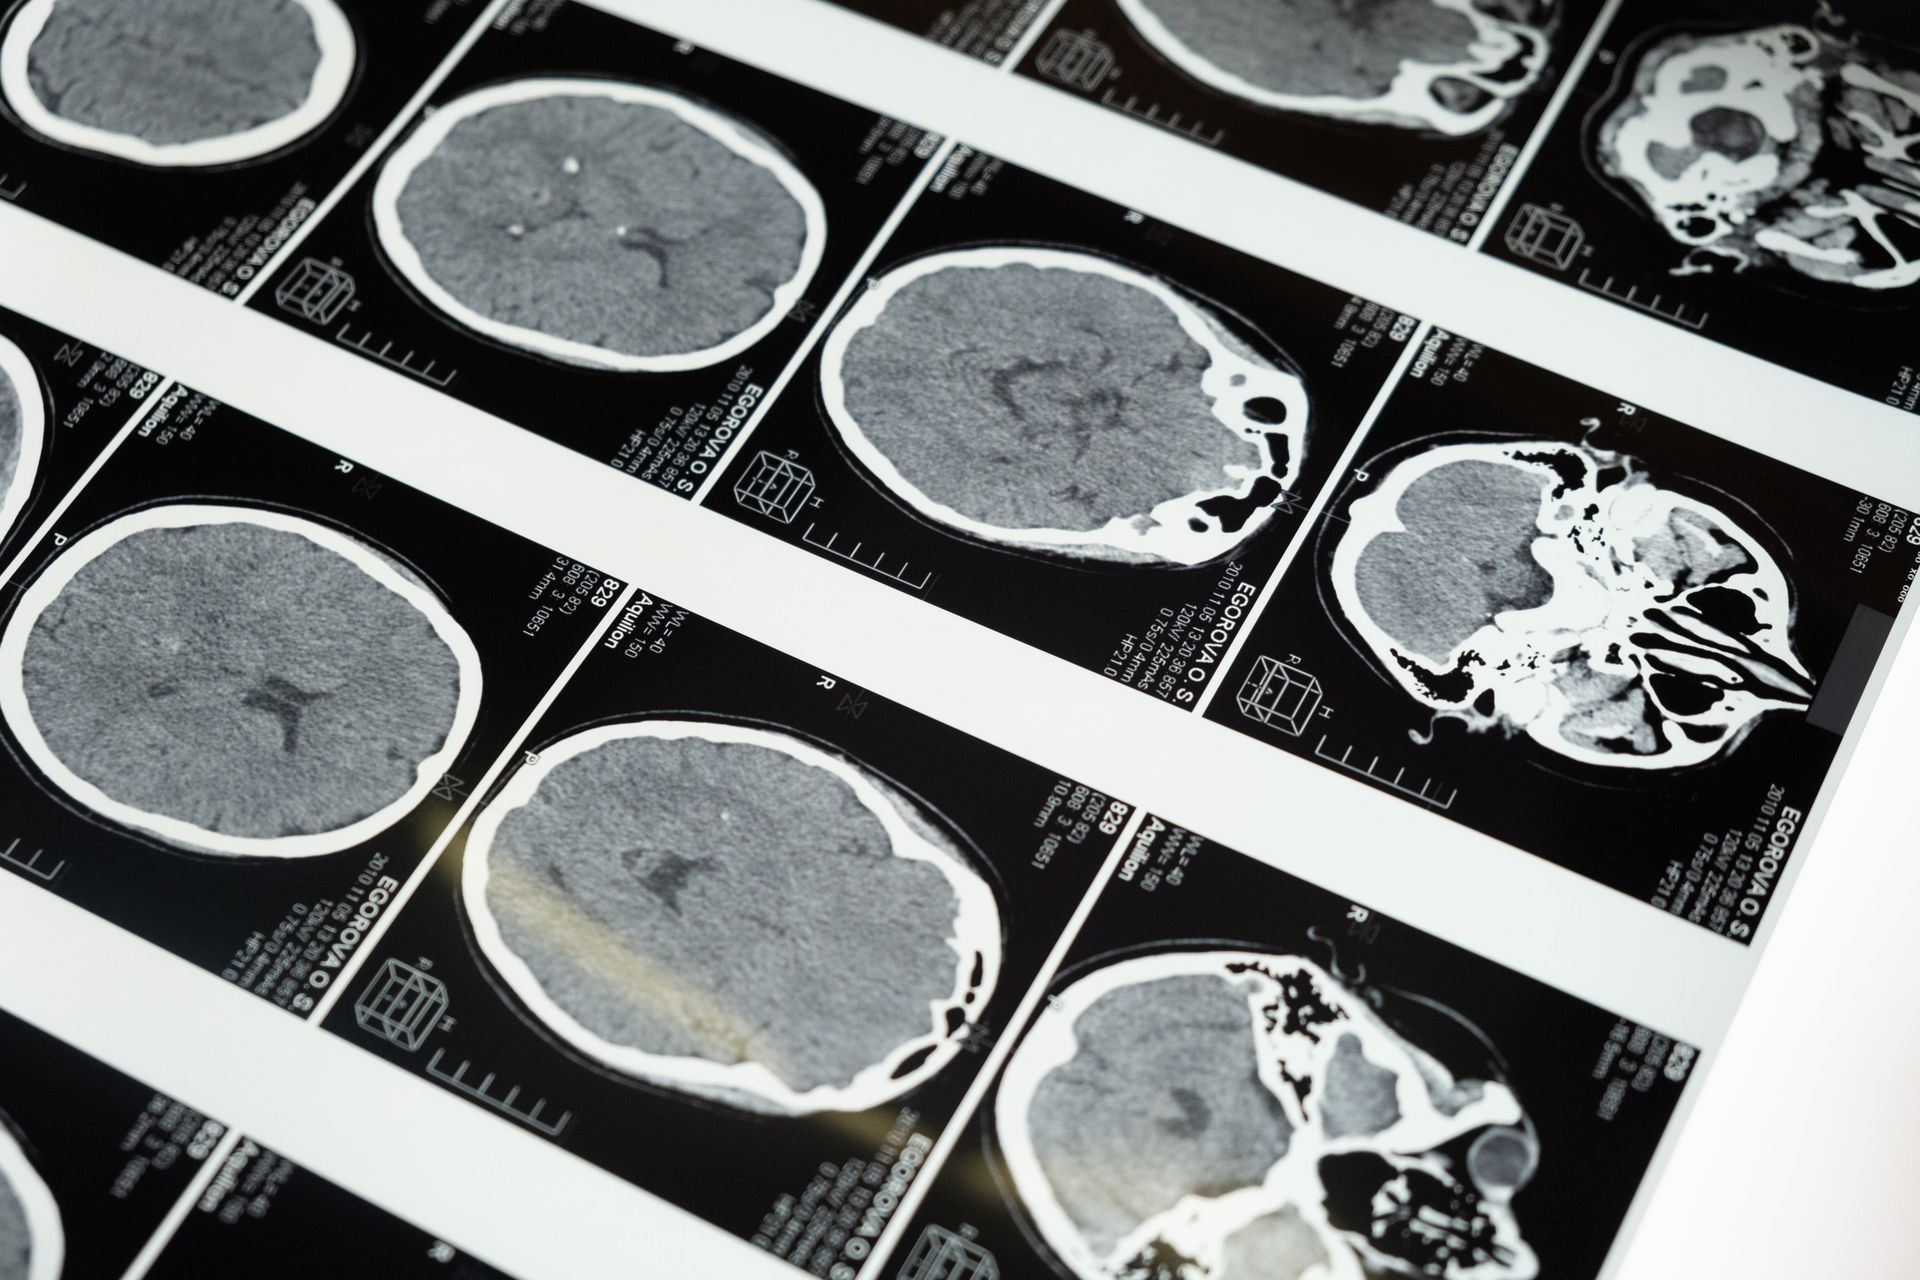

March marks the month dedicated to Traumatic and Acquired Brain Injury (TABI) awareness. This awareness focuses on topics including what a brain injury is (hint: concussions count), how common TBI’s are, prevention, and recovery (recovery is possible!).

Any external jolt to a person’s head which causes the 3lb jelly-like-mass in our noggins to bump around = traumatic brain injury. Common causes of TBI’s in Alaska include: motor vehicle accidents (ATV, snowmachine, or car), falls, assault, and unintentional injury to the head (State of Alaska Epidemiology, 2023).

Acquired brain injuries occur after birth via an internal mechanism rather than an external jolt to the head; such as strokes, aneurysm, tumor, insufficient oxygen supply to the brain, or infectious diseases (Brain Injury Association of America, 2022)

Since the brain is complex (and fantastic), it localizes functions in different regions of the brain. That is part of the reason why brain injuries are complicated: because the severity of injury is largely determined by two factors: (1) how severe was the injury, and (2) which region of the brain did the injury occur.